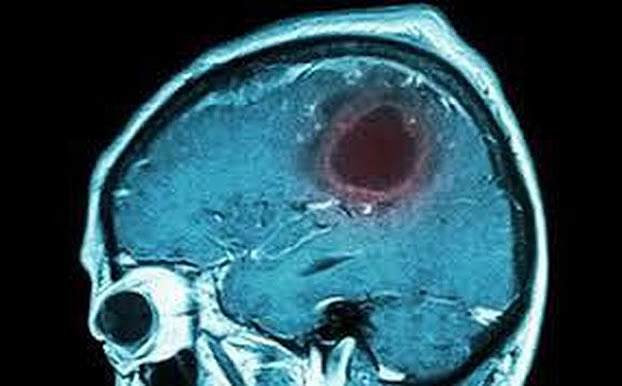

8 biểu hiện của bệnh u não cần cảnh giác

Hình ảnh u não